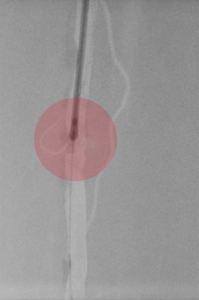

Für interventionelle Behandlungsmethoden ist ein Zugang ins Gefäßsystem notwendig. Dieser wird am häufigsten in der Oberschenkelarterie/-vene im Bereich der Leiste oder der Armarterie/-vene im Ellenbogen- oder Handgelenksbereich angelegt.

Dazu erfolgt nach gründlicher Desinfektion und lokaler Schmerzstillung die Nadelpunktion des Gefäßes mit anschließender Einführung einer Gefäßschleuse (Gefäßventil), die dem Behandler ermöglicht, unterschiedliche Kathetersysteme zur Behandlung ohne Blutungs- und Verletzungsgefahr schmerzarm in die zu behandelnde Gefäßregion einzuführen.

Nach der Behandlung wird der Gefäßzugang/Punktionsstelle wieder mit einem Verschlusssystem abgedichtet und ein Kompressionsverband von außen angelegt, damit es zu keiner unkontrollierten Blutung kommt. Zur Sicherheit ist eine mehrstündige Bettruhe einzuhalten.